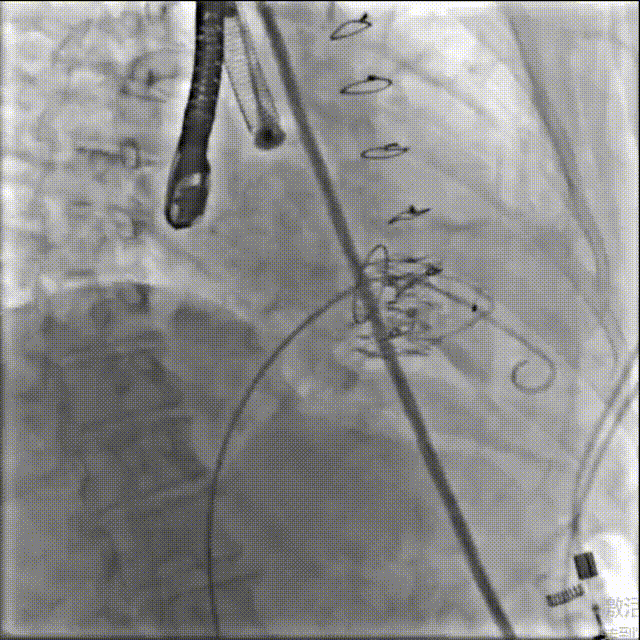

术前造影

图片

术中造影

术后造影